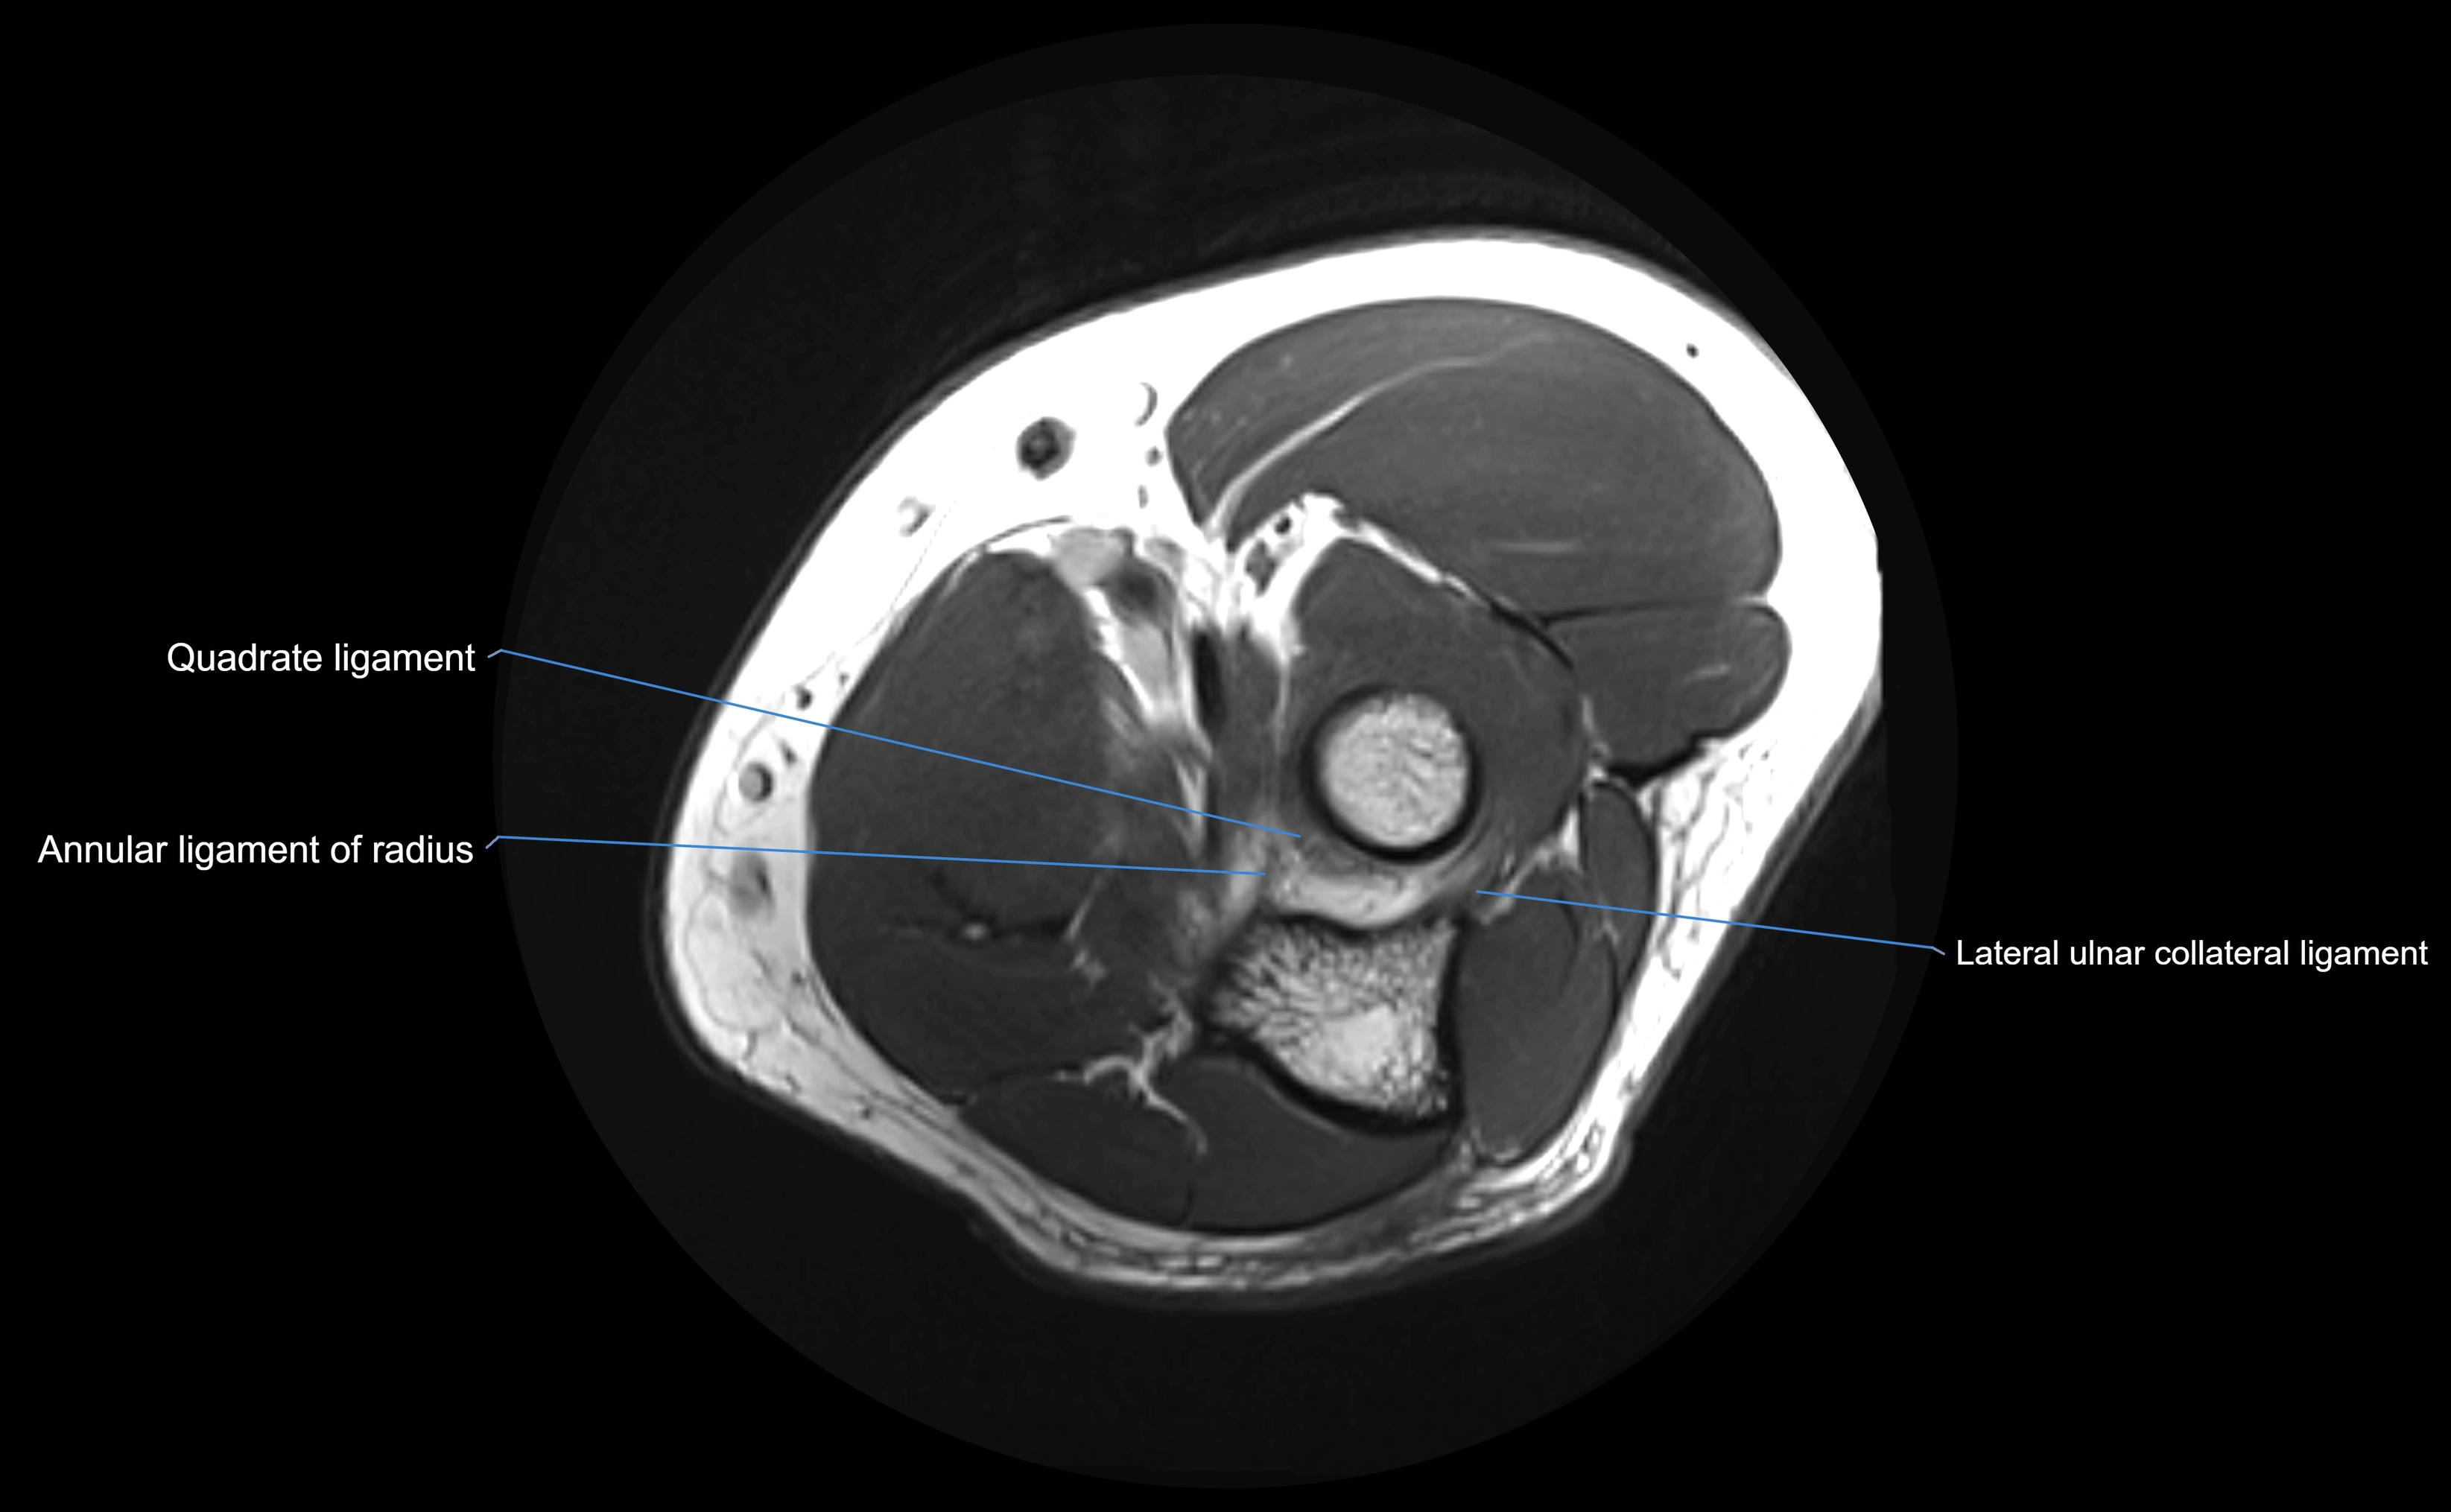

Annular ligament of radius

The annular ligament of the radius is a strong, circular band of fibers that encircles the head and neck of the radius, holding it securely against the radial notch of the ulna. It forms part of the proximal radioulnar joint, permitting smooth rotation of the radius during pronation and supination of the forearm.

The ligament acts like a collar or loop, maintaining radial head stability while allowing rotation. It is essential for forearm motion, elbow stability, and load transmission from the radius to the ulna and humerus.

MRI Appearance

T1-weighted images:

• Ligament: low signal intensity (dark), appearing as a continuous band around the radial head.

• Adjacent fat and marrow: bright, creating contrast with the ligament.

• Thickening or disruption indicates injury or fibrosis.

• Joint capsule and synovium seen as thin low-signal lines contiguous with ligament margins.

T2-weighted images:

• Ligament: low signal (dark) with clear delineation from joint fluid.

• Fluid or edema: bright hyperintense, separating or surrounding the ligament in partial tears.

• Complete tear: discontinuity or non-visualization of ligament fibers, often with joint effusion.

STIR:

• Normal ligament: dark band encircling radial head.

• Pathology: bright hyperintense periligamentous signal suggesting edema, sprain, or partial tear.

Proton Density Fat-Saturated (PD FS):

• Normal: dark, well-defined band outlining the radial head.

• Partial tear: irregular or bright hyperintense signal within or adjacent to ligament fibers.

• Joint effusion and reactive synovitis appear bright and are well visualized.